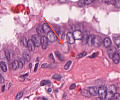

A100 M. Paget der Mamille

Epidermis mit Tumorinfiltraten basal und pagetoid (hohe Vergrößerung)

A100 M. Paget der Mamille

Tumorzellnester basal und Tumoreinzelzellen, die in bis in das Stratum corneum aufsteigen.